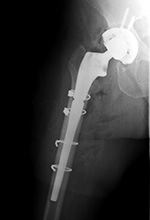

protrusio (Berquist, 1995; Benjamin, 1994). There are variations on the standard bipolar hip prosthesis with claw plates or cerclage wires used to stabilize the stem of the prosthesis (figure: bipolar hemiarthroplasty with claw plate).

| Bipolar hemiarthroplasty with claw plate and cables

|

Bipolar hip prosthesis with cable plate (cables passed through the plate) |

| 78 year-old woman with prior bipolar hemiarthroplasty; presently treated with claw plate and cables for intertrochanteric fracture.

The cable plate and wires stabilize a periprosthetic femoral shaft fracture. From Taljanovic, 2005 |